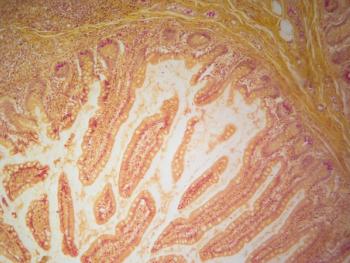

Findings presented at the 2026 Joint ASTCT + EBMT Basic and Translational Scientific Meeting offer potential therapeutic targets to reduce GI toxicity and GVHD.